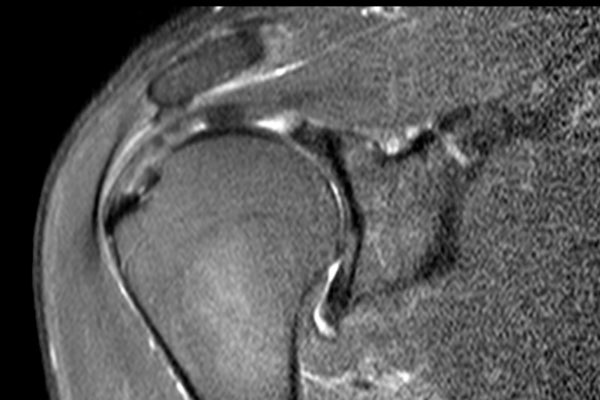

Có hình ảnh rách toàn bộ chiều dày phần trước của gân cơ trên gai, kéo dài từ mặt khớp đến mặt túi hoạt dịch.

Do các sợi gân phía sau của gân cơ trên gai còn nguyên vẹn, tổn thương này được gọi là rách toàn bộ chiều dày không hoàn toàn của gân cơ trên gai.

Không có co rút.